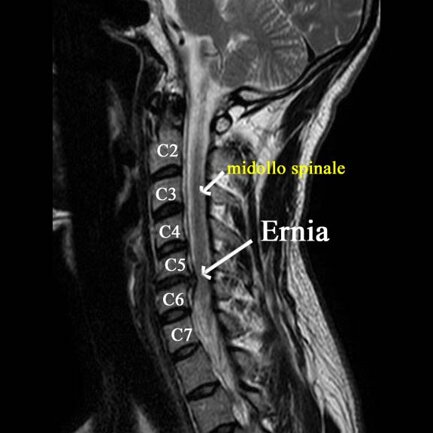

Acutissima e improvvisa comparsa di dolore al braccio sinistro, insopportabile che si accompagnava ad intense sensazioni di “scosse elettriche”, tale da costringere questa persona a dover cessare l’attività lavorativa e ogni attività sociale.

Una risonanza lombare ha ernia discale cervicale C5-C6 .

Non presentava disturbi di forza all’esame neurologico obbiettivo.

Optava per ozonoterapia.

Nel corso delle sedute (effettuate alcune con tecnica ecoguidata iuxtaradicolare C5-C6, utilizzo di ecosonordoppler vascolare, graduale diminuzione del dolore.

Alla fine delle 8 sedute (4 settimane di trattamento), regressione completa del dolore brachiale sinistro, con possibilità completa di mobilizzazione e graduale ritorno alla normalità e ripresa dell’attività lavorativa, senza assumere alcun farmaco.